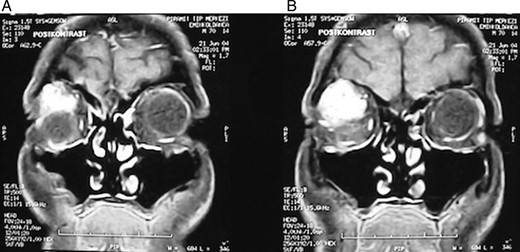

A 62-year-old male patient referred to our clinic due to painless exophthalmia of his right eye for the last 2 years. On neurological examination of the patient, there was no abnormality except for the up-gaze restriction and severe exophthalmia. Computerized tomography revealed an intraorbital mass in the right eye. A well-defined 2.5-cm isodense mass was located on the right lacrimal gland. The mass was contrasted homogenously (Fig. 1a and b). Cranial magnetic resonance imaging (MRI) revealed an isointense mass on the superolateral part of right orbita in the coronal intersections and it was contrasted homogenously (Fig. 2a and b). The existing score of our patient according to Rose and Wright was +8 points. Combined orbitofrontal craniotomy was performed through a transcranial approach. The well-defined, soft, white, 2.5-cm mass was removed completely. Exophthalmoses disappeared after the surgery (Fig. 3a and b). Histological examination of the surgical specimen covered the epithelial and stromal components that formed the glandular structures. Keratinized plugs were seen in some glandular lumens. Cartilaginous differentiation of stroma was found (Fig. 4a–d). Based on these findings, the tumor was diagnosed as pleomorphic adenoma. There was no recurrence after 8-year clinical follow-up.

(A and B) Cranial MRI revealed a homogenously contrasted mass on the superolateral part of the right orbita.